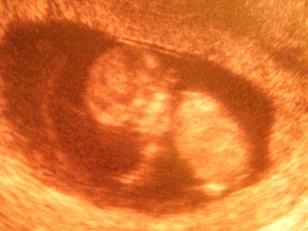

nekem 6+3-on volt 6,3 mm es ülőmagasságú a baba :D :shock:

Meggymag, az nem az én méretem, hanem a húgomé, aki 6+2 ma! :D :D :D

Az én babóm 6+2-nél 2 mm volt, és tudom, hogy egy héttel kisebb is volt! 8)